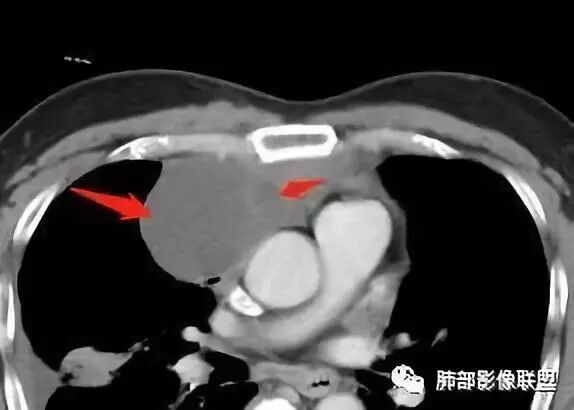

Coke with ice:囊性部分考虑包裹性积液?南边:不是积液;有间隔;张力高;而且位置有些特殊

大家仔细看看积液中的游离气体;

不是支气管,是积气;是穿刺进去的;

囊内密度不一致

我认为囊张力高,积液中的气体均在周围,外侧、下方,囊内有间隔:各腔密度不一致;提示:囊腔属于前纵隔,不是包裹性积液;现在的问题:囊腔与内侧的病灶是否是一体的